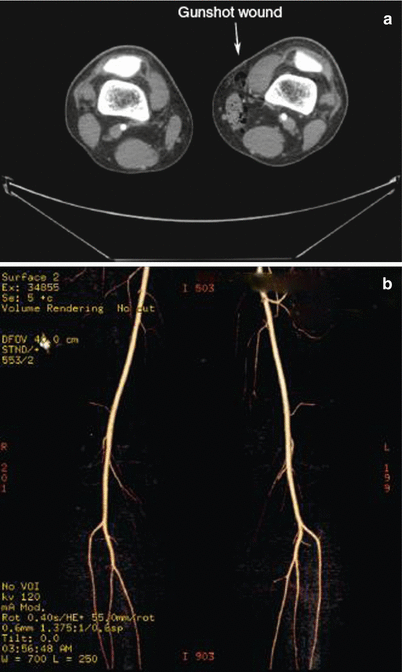

Fig. 16.9

(a) Gunshot wound to the left lower extremity. No evidence of significant bony or vascular injury. Treated with local wound care. (b) CTA reconstruction of lower extremity vasculature demonstrating no evidence of vascular injury

In the radiographic evaluation of extremities for vascular injuries, conventional angiography has long been considered the gold standard. However, over the past several years with the development of multidetector CT scanners, CT angiography has been shown by several authors to offer both a high sensitivity (95–100 %) and specificity (87–100 %) for the detection of injuries, without the potential drawbacks of conventional angiography such as access site thrombosis, groin hematoma, distal plaque embolization, or intimal dissection. When the use of CT angiography was retrospectively evaluated at an urban US level 1 trauma center, Peng et al. found that its use effectively ruled out injuries in 55 % of studies and was associated with zero false negatives or missed injuries as well as excellent correlation between CT angiography results and operative findings in patients who had injuries identified and subsequently underwent operative exploration. Furthermore, the authors noted that by the end of their study period, CT angiography had become the radiographic study of choice in the initial evaluation of extremity vascular trauma at their institution. Another review of the technique by Soto et al. at a Columbian trauma center demonstrated excellent sensitivity and specificity (95 % and 98 %, respectively) with one false-positive result over 139 patients. The authors did point out that almost 4 % of the studies performed were so degraded by scatter artifact from retained metal fragments that they were non-interpretable. Injuries were effectively ruled out by 55 % of the interpretable studies (Fig. 16.10).